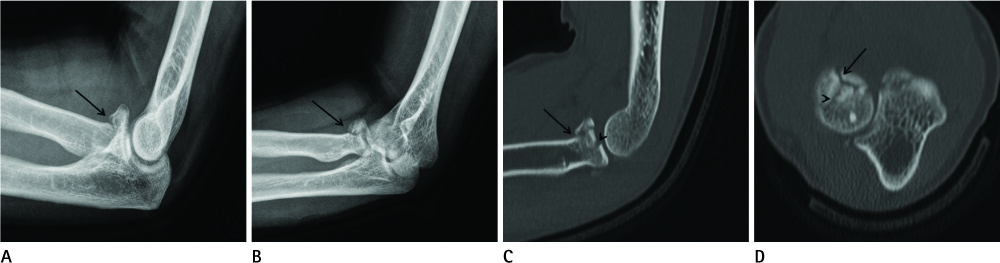

Diagnostic Value of Multidetector Computed Tomography in Radial Head or Neck Fractures

To evaluate the diagnostic value of multidetector computed tomography (MDCT) in radial head or neck fracture, and to evaluate factors that affect MDCT image quality.

Sixty-six radial fractures in 65 patients, who underwent both radiography and MDCT, were included. Detection of fracture and classification of types were recorded for each modality. Patients were divided into the good (A) and poor (B) image quality groups, and recorded the factors, such as arm positioning, flexion angle, and cancellous bone density.

The detection rate of fracture showed no significant difference between the two modalities. However, classification of the fracture type was significantly accurate by MDCT (p < 0.0001). Eight cases were only detected on MDCT and three cases were only detected on radiography. Fracture type was discordant in 11 cases. MDCT scanning with raising arm (p < 0.0001), with lesser flexion angle (p = 0.004), and higher cancellous bone density (p = 0.010) showed better image quality.

Radiography is a good primary tool for detecting radial head or neck fracture. However, MDCT can be an additional tool for classifying the fracture type and cases with negative radiographic findings. Arm positioning, flexion angle, and cancellous bone density affect MDCT image quality.